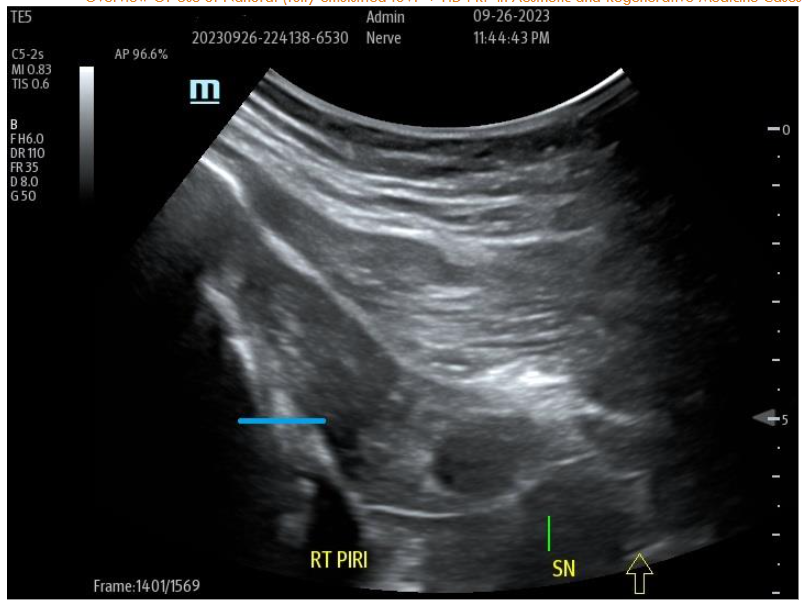

Many examples of important epineural-dissections and fascial inflammatory conditions have been improved with applications of a biocellular mixture, including use of PPP products are becoming a very common, safe and effective protocols. Often by “resting” simulated, entrapped or irritated peripheral sensory nerves, long-term relief is attained. This is considered partially due to fibrin conversion which may provide addition protection while reducing the nerve axonal irritation. This has become a more effective and commonplace option, particularly in areas such as inflamed fascia as in the thoraco-lumbar fascial (TLF), Piriformis/Sciatic areas, and Ilio-Tibial Band (ITB). The PPP or biocellular elements are also capable of providing soothing impacts of the area, plus helping limit inflammatory response and promote recovery. It may be a combination of the anti-inflammatory action of the stem/stromal cells and the fibrinogen contained to form a fibrin protection of irritated nerve structures often missed in regenerative efforts and not available in invasive surgical procedures.

Figure 9A: Pre-Treatment U/S of degenerative Piriformis (sciatic radicular symptoms) no history of trauma, degenerative Pattern within Piriformis musculature with loss of muscle echotexture. Figure 9B: Post-treatment of site at nine months post-treatment with tSVF + HD PRP (70% tSVF: 30% HD PRP (6X – concentration HD PRP) with return of improved muscular echotexture and elimination of radicular sciatic symptoms.